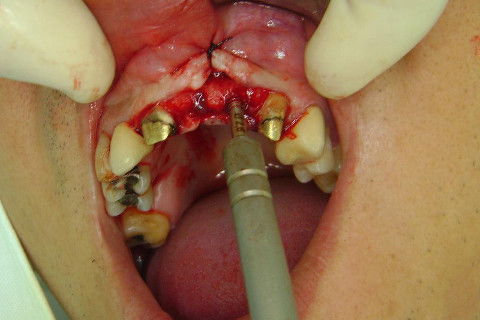

Cirurgia realizada hoje de manhã...No planejamento percebi medindo espessura do rebordo com especímetro que as medidas não estavam muito boas, ou o ideal, em torno de 4,5 a 5 mm ate´o terço médio do rebordo e melhorava no final, com 6 a 7 mm. Optei então por uma pequena expansão usando os expansores rosqueáveis. Aconteceu uma pequena fenestração na hora da fixação dos implantes, especialmente na região do 22 que fraturou o início da tábua óssea, mas não me preocupei porque não foi mais do que 2 mm de fratura em direção apical, o implante ficou infraósseo e com boa estabilidade (60 N no 21 e 40 N no 22). Esta fratura tb não deixou osso completamente solto, foi do tipo galho verde, deixei em posição e suturei normalmente. Só não fiz e nem estava planejado carga imediata mesmo, mais pelo motivo da oclusão inadequada do caso.

Fotos do caso